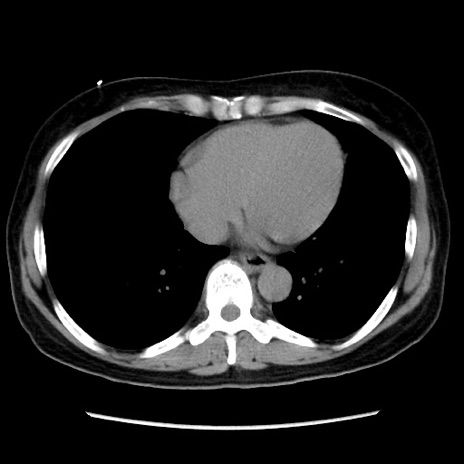

冠状断像